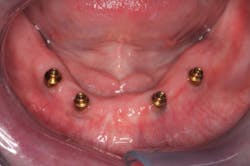

Tip no. 3: Use more implants

It is widely noted that a minimum of two implants are required in the mandible for removable dentures.5 Four or more implants are optimal for the maxilla.6 These minimums can be successful more than 85% of the time, but long-term success can be increased by adding additional implants (figure 4).7 Balaguer et al. studied 95 patients over an average of six to nine years and found that survival rate in the maxilla of four implants was 85.7%. Survival rate of six implants was 100%. In the mandible, survival rate of two implants was 96.6%, whereas survival rate for three implants was 100% and survival rate for four implants was 99%.7

Adding additional implants reduces stress on each individual implant. In most cases, it helps ensure that if an implant is lost, there will be enough remaining implants for a successful case. In the mandible, additional implants will increase retention and, therefore, patient satisfaction. We offer financial incentives for our patients to add additional implants. It’s a win-win. Our patients enjoy greater security and success, and we invest less clinical time on adjustments and addressing complications.

Tip no. 4: Select ideal implant positions

Choosing ideal implant positions reduces stress on the implants and lessens complications. A consensus on the ideal positions in the maxilla is difficult to find, but in both maxillary and mandibular arches, the implants should be equidistant from the midline and evenly spaced.8,9

For two mandibular implants, place the implants in the positions of the canines or lateral incisors. Implants distal to the canines will be posterior to the anterior fulcrum line, which will result in more stress on the implants. For three implants, ideally place them at the midline and in the canine positions. Four implants should be placed at the sites of the lateral incisors and the first bicuspids.10